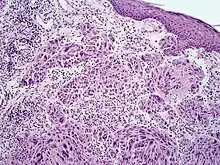

Melanoma with features of a Spitz nevus

Melanoma with features of a Spitz nevus (also known as a "Spitzoid melanoma") is a cutaneous condition characterized histologically with tissue similar to a spitz nevus and with overall symmetry and a dermal nodule of epithelioid melanocytes that do not mature with progressively deeper dermal extension.[1]

Spitzoid melanoma